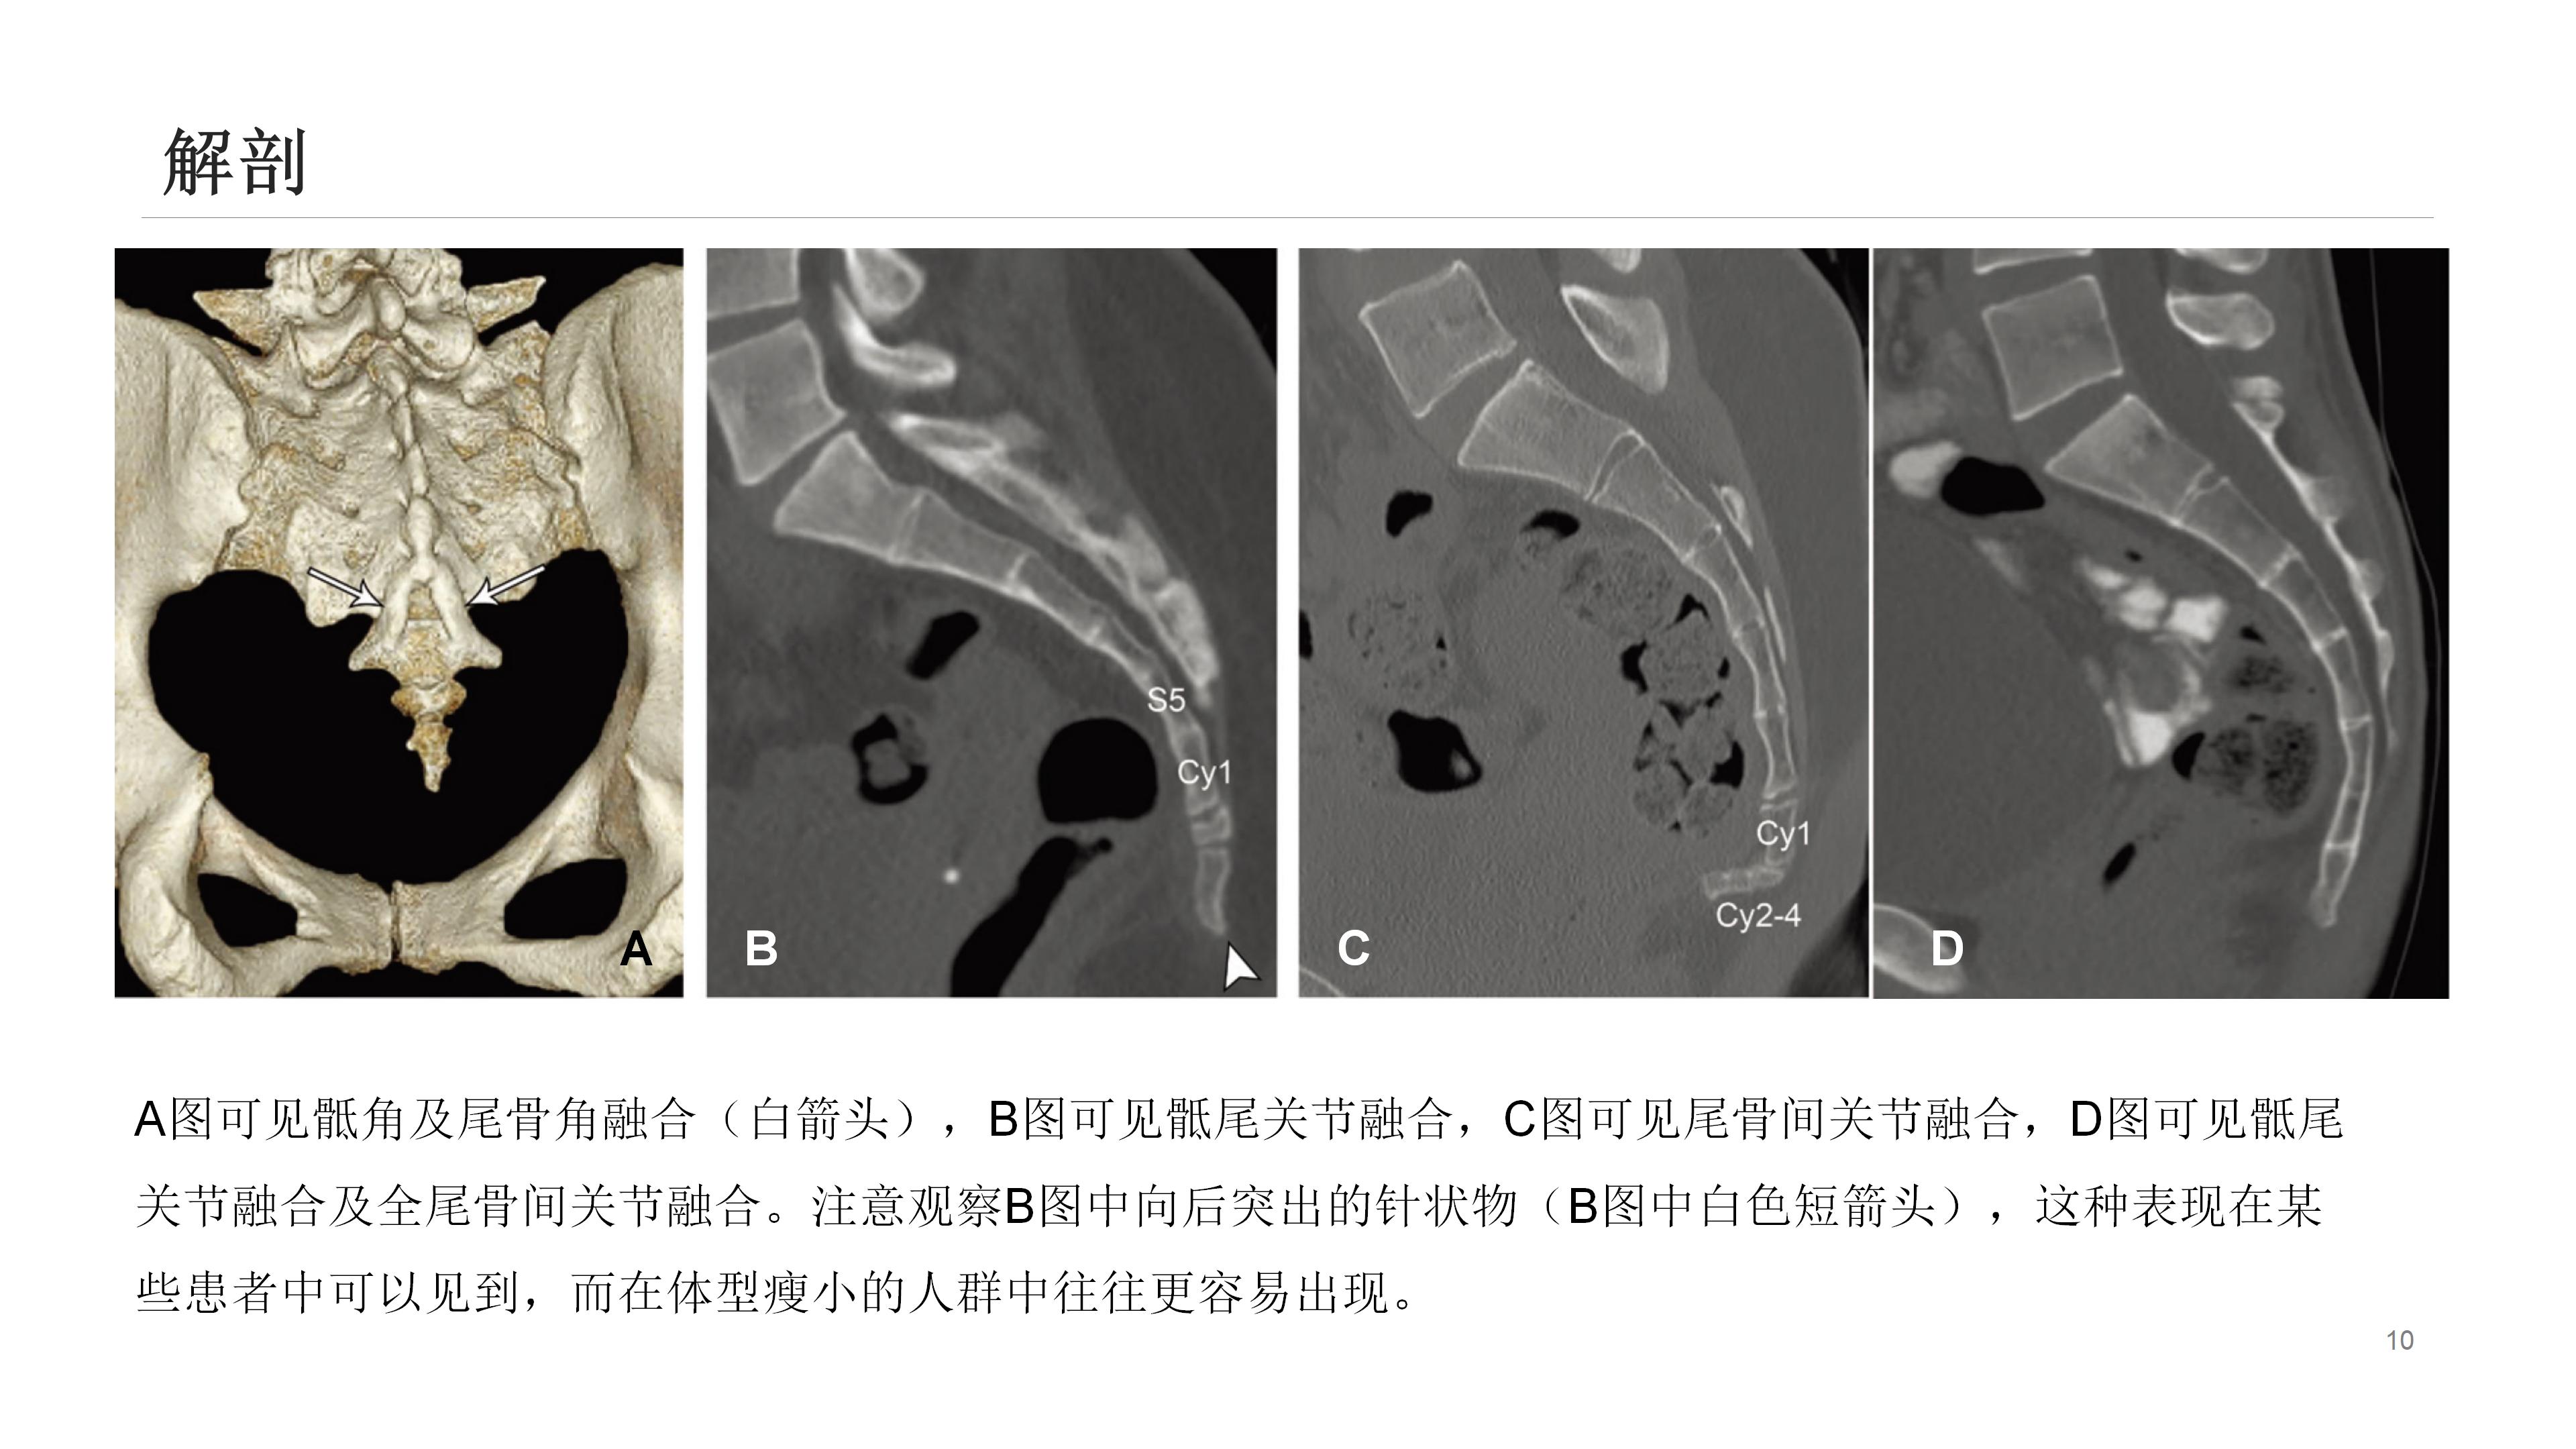

尾骨区域解剖结构复杂,众多结构皆可能引发该区域疼痛。影像学能出色呈现其解剖学特点,辨别受累结构可指导临床处置。尾骨疼痛乃常见临床症状,却难以评估和治疗。

通常,尾骨疼痛多在创伤后出现,初始静态平片检查可能正常,而动态平片(站立位及坐侧位平片)或可观察到异常尾骨移动,以此解释疼痛来源。